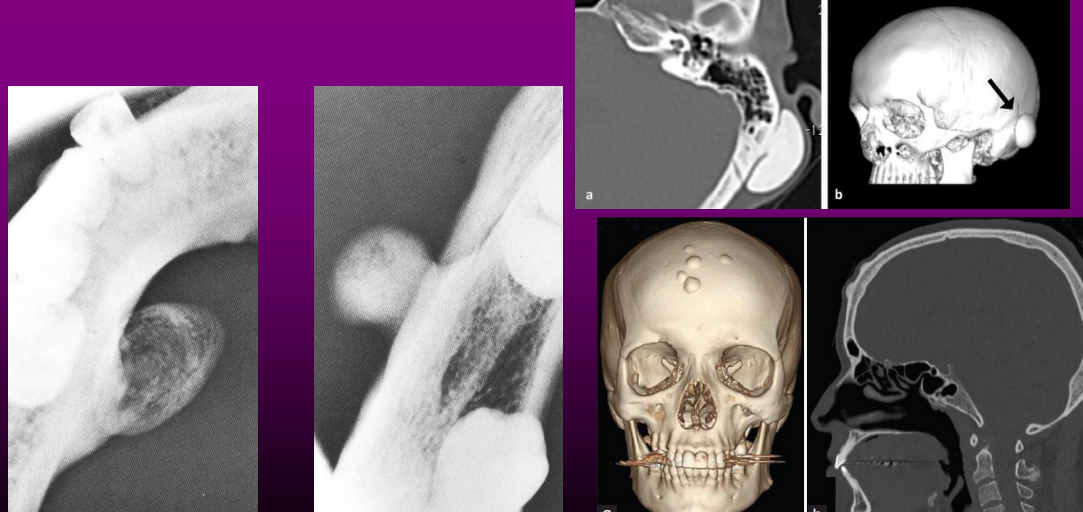

*Alteração progressiva na oclusão do paciente.

*Desvio da linha média em direção ao lado afetado, má oclusão.

*Tumefação facial.

*Dor e limitação na abertura da

boca.

*Para distinguir hiperplasia condilar de osteomas:

os osteomas condilares são lobulados

hiperplasia do côndilo mantém sua forma original

• São mais comuns que as lesões gnáticas.

Geralmente assintomáticos. Sintomas como sinusite, rinorréia, podem invadir a órbita e causar proptose, diplopia e diminuição da acuidade visual.

• Seio frontal é o mais envolvido, seguido pelo etmoidal e maxilar